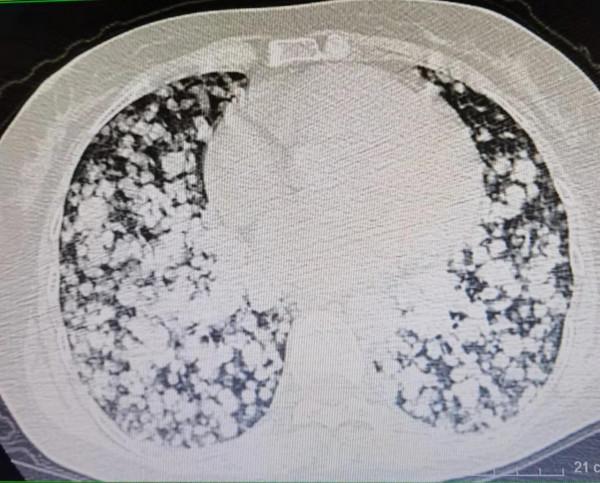

看到這個病人的胸部CT影象,我驚呆了,從醫這麼多年,真的沒見過這麼恐怖的影象,整個肺部就像滿布的雪花,又像蜂巢一樣千瘡百孔。可以說殘存的正常肺組織很少,全部被腫瘤佔據了。然而更為嚴重的是,腫瘤已經侵犯浸潤到氣管,她的氣管狹窄變扁,而咳血和氣喘主要也是由於氣管這裡的病變引起的。

這是這個病人的肺部CT:

這個病人是11年前患甲狀腺濾泡癌,當時做了甲狀腺部分切除手術,術後前兩年複查沒有太大問題,之後再也沒去過醫院,自己服用不清楚什麼成分的偏方,半年前就發現幹活之後氣喘,一直拖著沒去看,這次是咳血了才想起來到醫院檢查,這個肺部的影象屬實把大家都咋了一跳,“千瘡百孔”來形容一點不為過。這就是典型的肺轉移癌。這個病人已有呼吸衰竭的表現,需要立即吸氧,最後趕緊讓其到急診搶救。